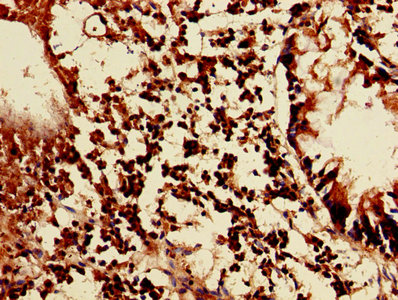

Immunohistochemistry of paraffin-embedded human appendix tissue using CSB-PA012721LA01HU at dilution of 1:100